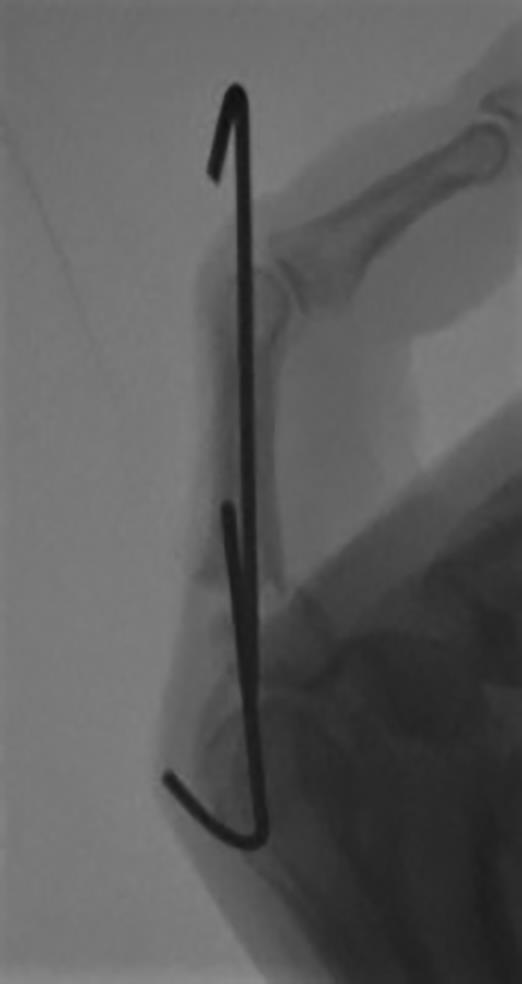

Figure A demonstrates AP and oblique Xrays of the index finger with a transverse fracture of the base of the proximal phalanx with apex volar angulation. Figure B demonstrates a lateral fluoroscopic image of the index finger proximal phalanx with an apex volar malunion.

Illustration A shows the corrective osteotomy to the malunion in Figure B with percutaneous fixation with Kirschner wires.